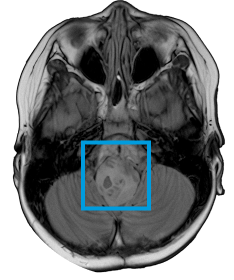

THIS CHILD HAS A BRAIN TUMOR

The first and only type II RAF inhibitor for BRAF alterations in relapsed or refractory pediatric low-grade glioma (R/R pLGG)1

OJEMDATM (tovorafenib) is indicated for the treatment of patients 6 months of age and older with relapsed or refractory pediatric low-grade glioma (LGG) harboring a BRAF fusion or rearrangement, or BRAF V600 mutation.